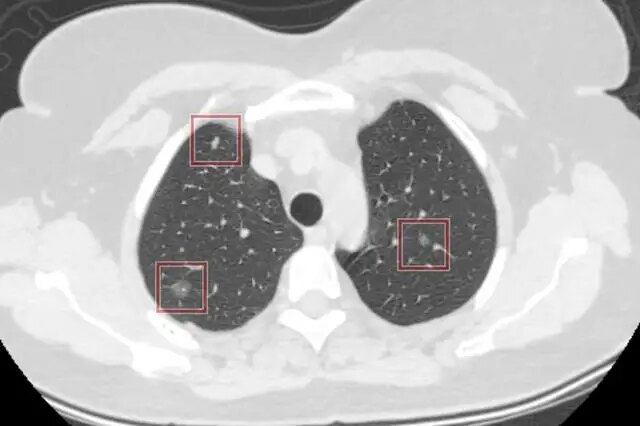

1、CT检查:如果肺部出现磨玻璃结节,可以及时到医院进行局部CT检查。如果属于良性结节,边缘会比较清晰,而且没有明显的毛刺或分叶。但是如果存在恶性结节,可能会出现空洞或空洞壁光滑的现象。

2、外形:良性结节一般体积会比较小,生长速度比较缓慢,而且并不会出现高密度影的现象。但是恶性结节一般体积会比较大,而且多发结节较多,生长速度也比较快,同时还会伴随局部高密度影的症状。

小于5mm的磨玻璃结节建议定期随访,对于3mm的结节一定是定期随访,太小也不适合做手术,可以通过系统的抗炎治疗或者通过中药辨证论治,看3mm的磨玻璃结节是否能够消失。消失说明是良性或者感染,如果没有消失需要继续定期随访。如果3个月内没有变化可以6-12个月随访一次,假如结节迅速变大、形态变化,说明恶变的可能性比较大。